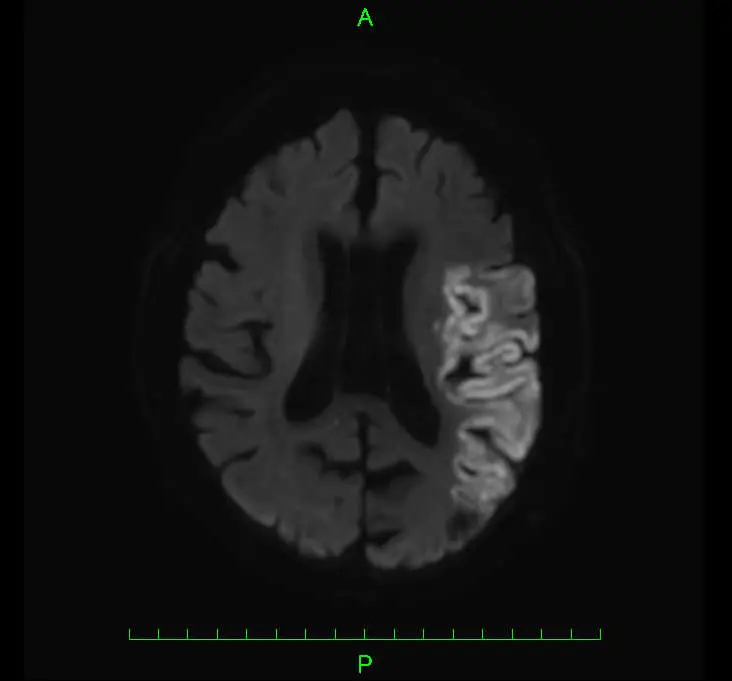

主に頭部MRI検査および頭部CT検査を用います。CTやMRIで脳梗塞と診断された場合は、原因の特定等を目的に心臓超音波検査や頸動脈超音波検査、心電図検査などを行います。

左内頸動脈閉塞の治療例